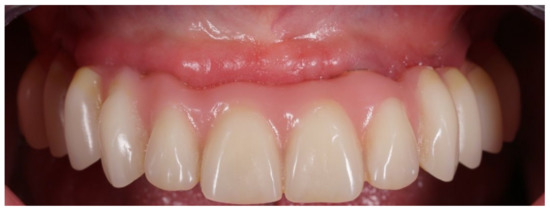

Figure 4.

Interim prosthesis without cantilevers.

Figure 5.

Interim prosthesis after implant placement.